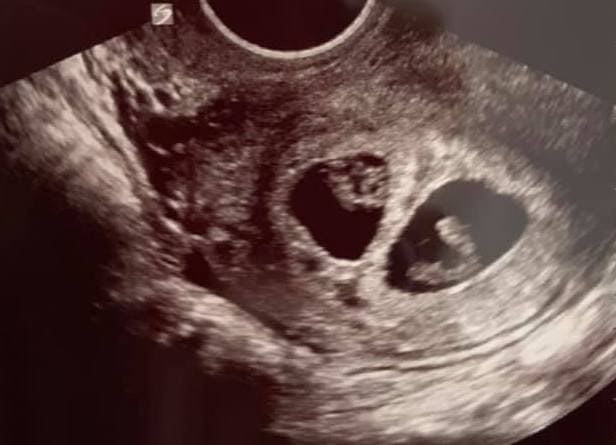

Early Twin Ultrasound at 7 Weeks

The earliest your doctor would likely order an ultrasound confirming twins would be 4 weeks pregnant. But unless you are going through fertility treatments, doing an ultrasound before 6 weeks isn’t very common, with the exception of complications. Women who are going through fertility treatments or have early complications may be able to have an early twin ultrasound at 4 or 5 weeks pregnant and find out they are pregnant with twins.

At four to five weeks after a pregnant woman’s last period the ultrasound commonly shows a small collection of fluid within the lining of the uterus that represents the early development of the gestational sac. At about five and a half weeks after a pregnant woman’s last period the ultrasound typically shows a gestational sac and within it we can see a 3-5 mm bubble-like structure, which is the yolk sac. At approximately six weeks after a pregnant woman’s last period, we can see a small fetal pole, one of the first stages of growth for an embryo, which develops alongside the yolk sac.

Yes! You’d need to have an ultrasound at 7 weeks to confirm a twin pregnancy. Your twin belly at 7 weeks may not look like much of a belly at all, so getting in to your doctor for an ultrasound is key to find out if you’re really having twins.